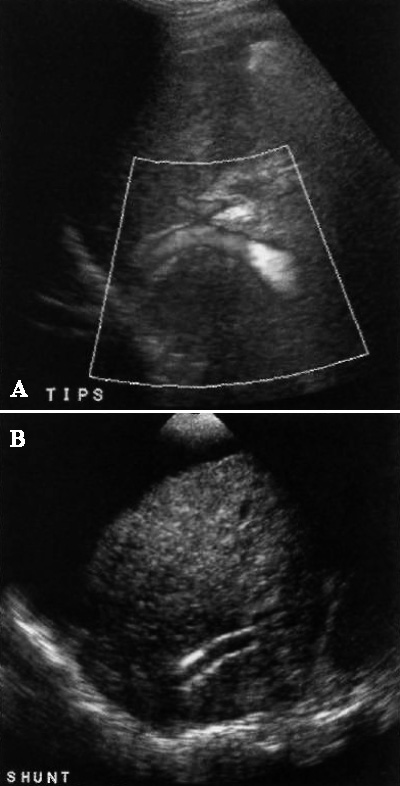

Трансъюгулярный внутрипеченочный портосистемный анастомоз (TIPS) – распространенный вариант портосистемного шунта, который устанавливают чрескожным доступом с целью разгрузки воротной венозной системы. TIPS прежде всего применяют при патологиях печени в терминальной стадии, чтобы предупредить развитие возможных осложнений до момента трансплантации печени. Функционирующий шунт позволяет снизить выраженность асцита, уменьшить портальную гипертензию, предупредить кровотечение из варикозно-расширенных вен пищевода. При этом установленные анастомозы подвержены стенозам и окклюзиям.

Проксимальный конец TIPS находится в главном стволе или правой ветви воротной вены, дистальный – в правой почечной вене, возле места ее соединения с нижней полой веной (фото 10).

Фото 10. Трансъюгулярный внутрипеченочный портосистемный шунт (TIPS) в норме. А – усиленная допплерограмма демонстрирует нормальную проходимость шунта. В – типичное ультразвуковое изображение TIPS в режиме серой шкалы